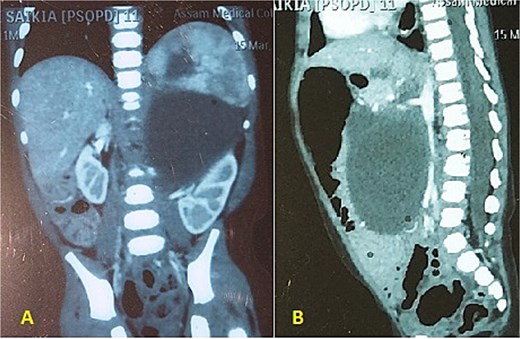

An 11 and half month old female child born out of a non-consanguineous marriage presented with lump abdomen and recurrent upper RTI of 3 months duration. The child was breast fed till 7 months of age and then supplemented with rice, dal, etc. The baby had normal weight gain till about 7 months (9.5 kg), but recorded 8.8 kg at the time of presentation. No urinary or bowel symptoms were present. The parents noted a lump in the abdomen at 7 months of age, which gradually kept increasing. An ultrasonography revealed a large multiloculated cystic lesion of 14 × 9 cm dimension in the retroperitoneum. Her haemoglobin level was 10.1 gm%. Other blood parameters were within normal range. Chest X-ray was normal. A contrast CT scan showed a multiloculated cystic lesion with thick septations displacing abdominal organs in the left retroperitoneum (Fig. 1A and B). Serum β-HCG level was within normal range and α-fetoprotein level was marginally raised. The child was admitted and operated through a left transverse upper abdominal incision. The left colon was mobilized and retracted medially; the pancreas, stomach, and spleen were retracted. The vessels supplying the tumour from major vessels were divided between ligatures. The tumour was mostly cystic with solid elements located posterior-superiorly. The tumour could be mobilized from the left kidney and adrenal, the spleen, pancreatic tail, and pelvic organs and was excised safely. There was no connection with the spine. The abdomen was closed without a drain. The mass weighed 550 g and had cysts of variable sizes with mucoid content (Fig. 2). Solid elements had soft tissues without any bone or haemorrhagic area. Hundred millilitre of packed cell was infused post-surgery. The patient was allowed feed 12 h post-op, had an uneventful recovery and was discharged on post-op day 4. She has been on follow-up since then and has normal activity and weight gain.

(A, B) CECT abdomen shows multicystic/solid mass pushing the abdominal organs.